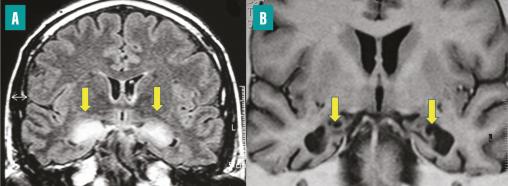

IRM cérébrale, coupes coronales.

Image A : séquences de diffusion. Hypersignal dans les deux hippocampes témoignant d’un œdème cytotoxique (flèches).

Image B : séquence en inversion-récupération. Séquelles atrophiques chez le même malade (flèches).